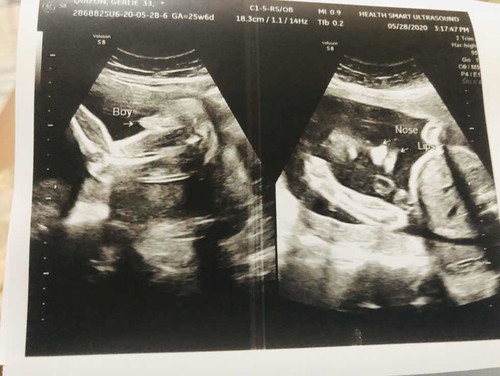

It’s a BOY??

Share ko lang result ng ultrasound ko! Super thankful kay God dahil binigay nya ung gusto namen na magka baby boy na after 7 yrs??.. and isa pa thankful din dahil before, low lying placenta ko pero sa dito sa last ultrasound ko okay na daw sabi ni ob.. antay ko na lang din umikot si baby kc suhi pa din.. and praying na wag muna lumabas kc masyado pang maaga.. sabi kc ni ob may contraction daw ako..kaya need ulit uminom ng pampakapit?.. may same case ko po ba dito na may contraction na din kahit masyado pang maaga para sa due date?